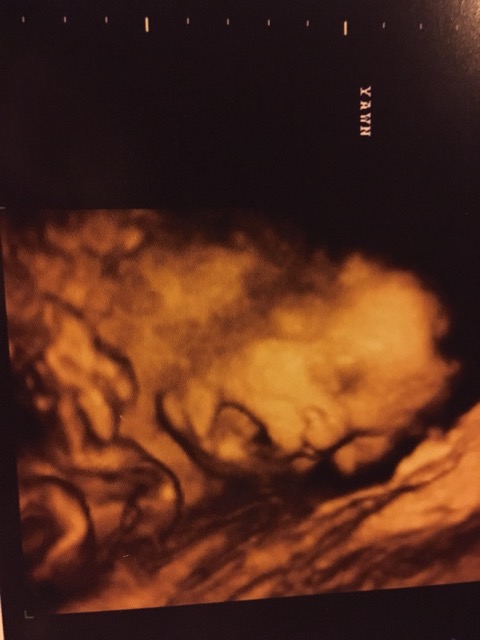

3D/4D ultrasound.

The yawn!

28weeks 4 days!